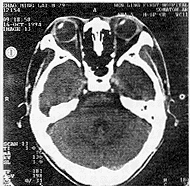

内直肌紧贴眶内侧壁自起点直线前行,附着于眼球前段。外直肌沿眶外侧壁弧形前行,附着于止点。双眼肌圆锥被视神经隔成内外侧腔,其外腔大于内侧腔。双眼侧方注视时,外展眼内外侧腔差异明显增大,外侧腔大于内侧腔,内转时内外侧腔大小差异不明显(图1)。